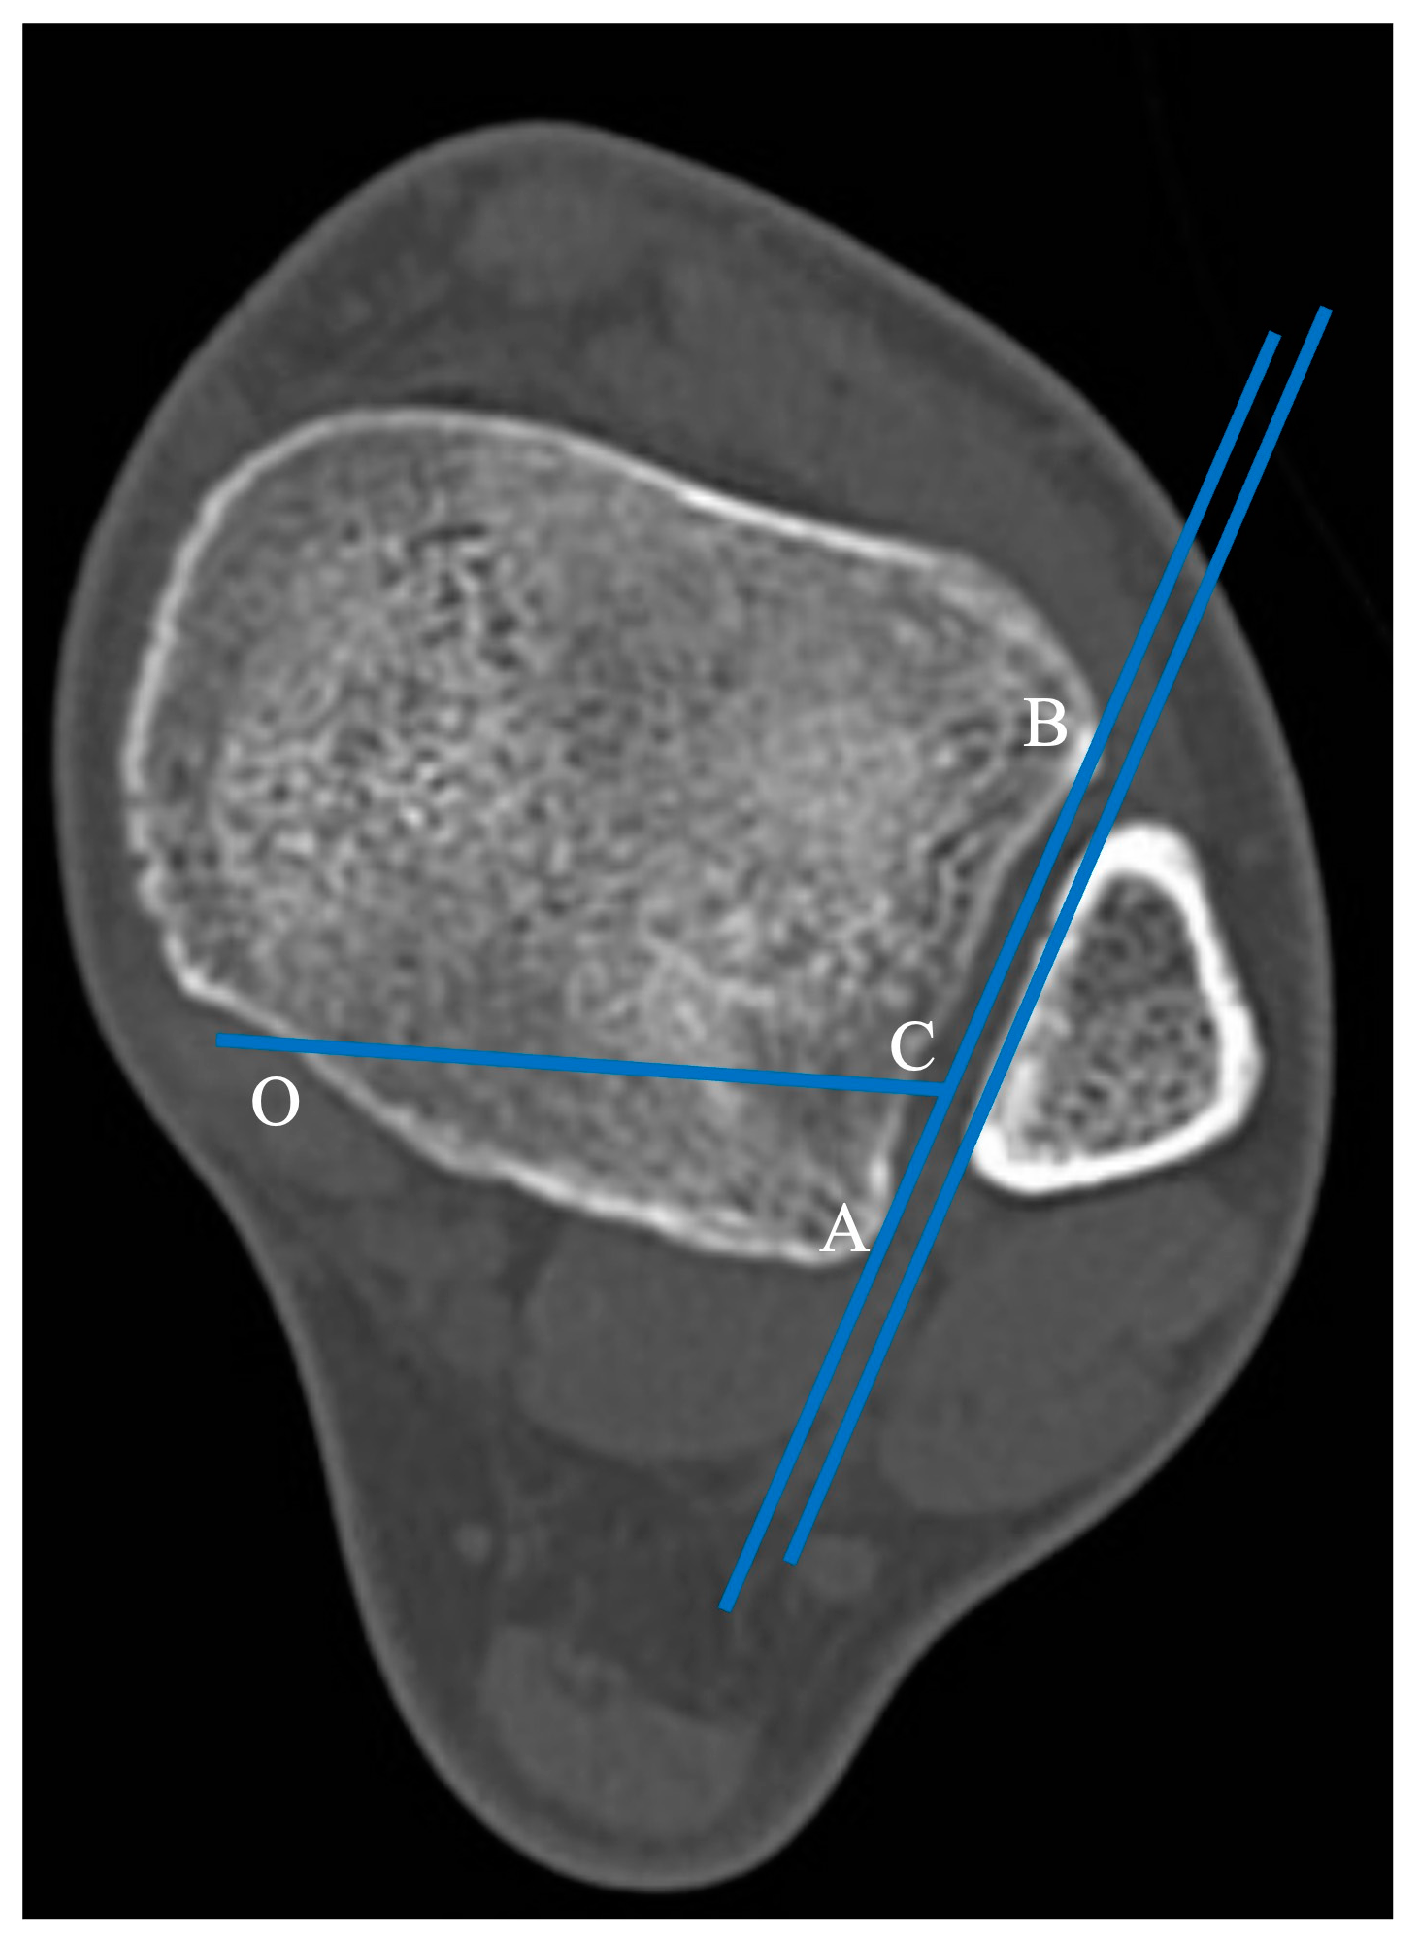

The horizontal projection of the distal articular surface of the tibia was taken as the reference plane. The AB projection line in the plane of the fibular notch and parallel to the medial fibula cortex was taken as a reference line and the point of intersection of the posterior ankle and medial ankle was point “O” [9]. The 1/4 point of the AB line was taken as point C. The intersection point of the posterior ankle and medial ankle was the “O" point, and the OC line was connected as the horizontal fracture line (Figure 2).

Figure 2. Axial cut of a normal distal tibia and fibula. The AB projection line in the plane of the fibular notch and parallel to the medial fibula cortex was taken as a reference line and the point of intersection of the posterior ankle and medial ankle was point “O”. The 1/4 point of the AB line was taken as point C. The intersection point of the posterior ankle and medial ankle was the “O" point, and the OC line was connected as the horizontal fracture line.